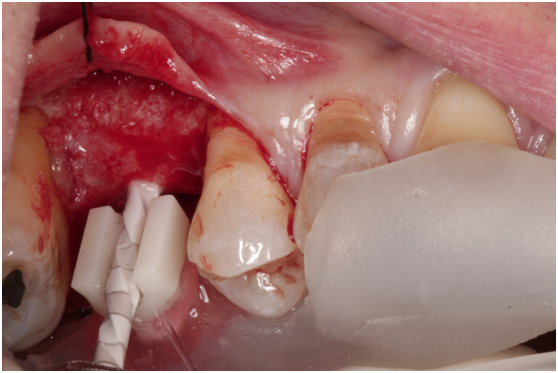

98/01/08經過三個半月做右下第一小臼齒的二階暴露,發覺鄰牙的植體高度竟已掉下來

980305幫患者補角化牙齦並翻開清除發炎組織,期待能阻止繼續骨破壞